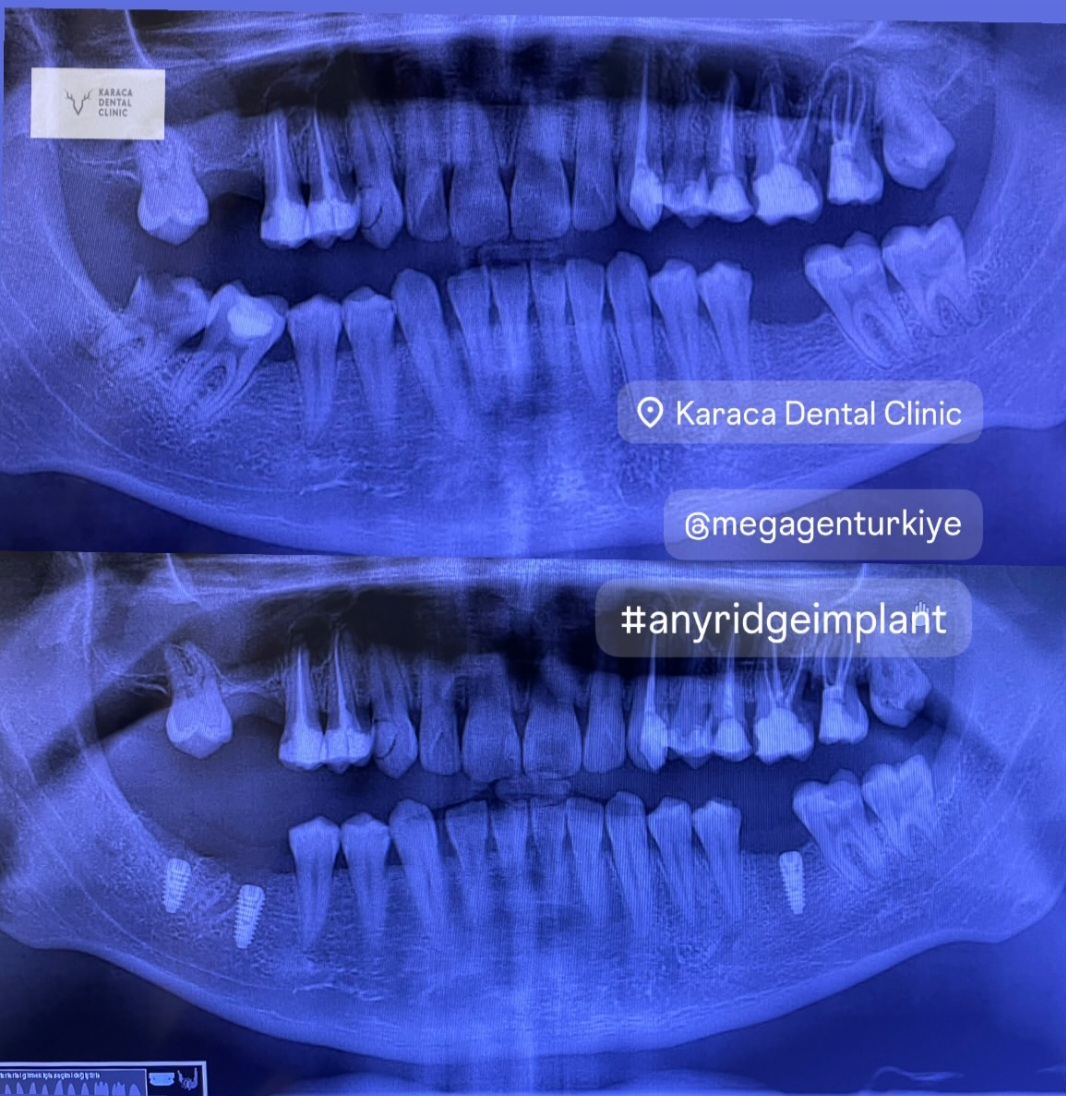

- Diş Dolgusu Kanal Tedavisi İmplant Tedavisi Çocuk Diş Hekimliği (Pedodonti) Lamina Kron Kaplama Zirkonyum Kron Kaplama Estetik Dolgu Estetik Gülüş Tasarımı Hollywood Gülüşü Diş Taşı Temizliği Air Flow Diş Temizleme Diş Beyazlatma Diş Çekimi Gece Plağı Dijital Diş Hekimliği 7/24 Diş Kliniği Hizmeti Acil Diş Kliniği Hizmeti Nöbetçi Diş Kliniği Hizmeti # HİZMETLERİMİZ #